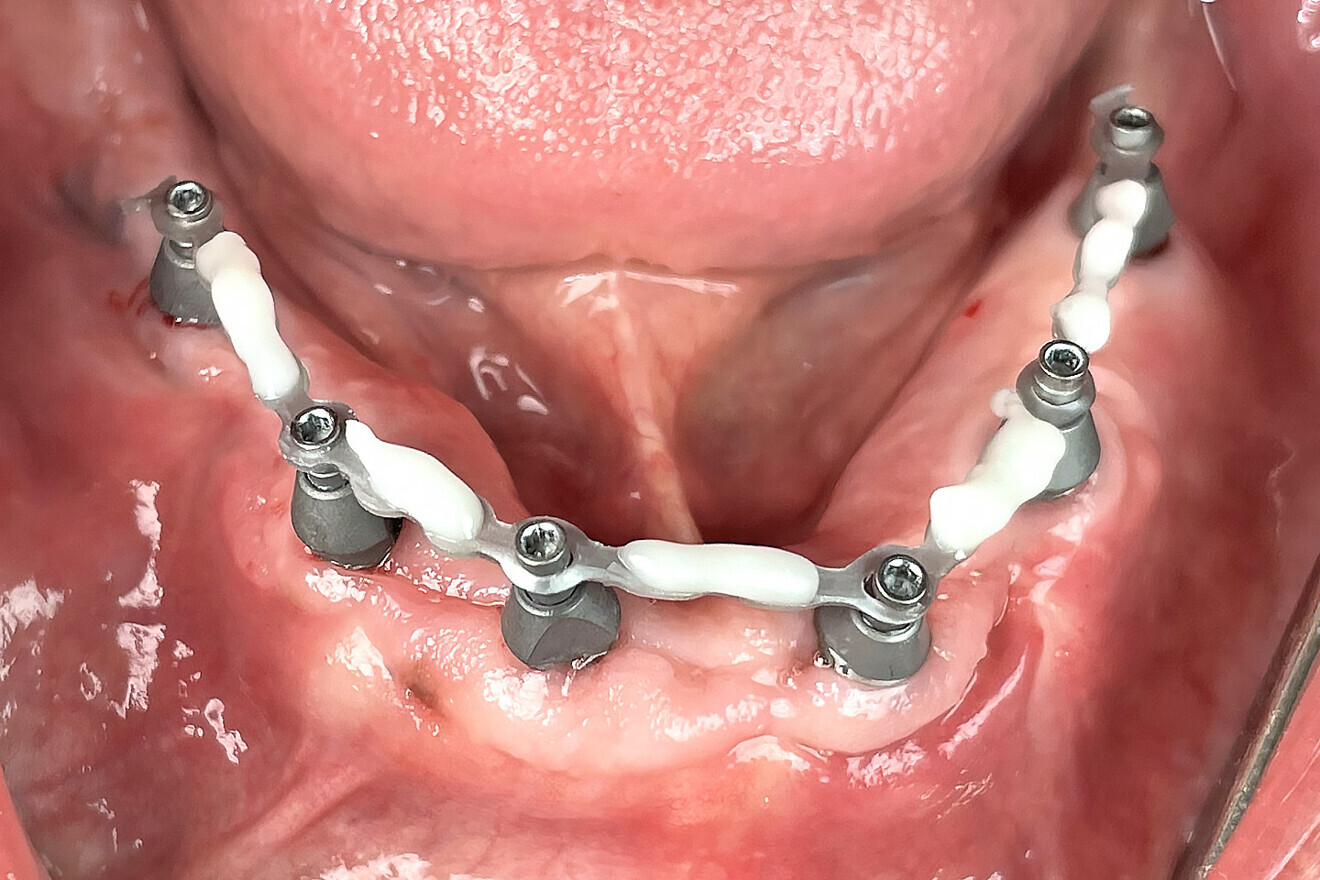

The analogue–digital process utilises MUA-compatible scan bodies (OptiSplint) designed to incorporate an aluminium mesh frame (Fig. 3a) that can be customised chairside (with the snipping tool included) as required by the intra-oral location of the implants. This mesh frame comes in small and large sizes to accommodate various mouth sizes and MUA–implant positions. The workflow involves inserting the scan bodies on to the MUAs intra-orally (Fig. 3b). The proprietary scan bodies have extensions (Fig. 4) to allow the mesh to seat and rotate in close proximity to the extensions, which facilitate luting using a resin base material (STELLAR DC Acrylic, Taub Products). The structure can then be digitised by scanning intra-orally with an intra-oral scanner and extra-orally with an intra-oral scanner or desktop scanner. The bonded splinting of the scan bodies to the mesh frame allows for a simple uninterrupted scan path.

Fig. 3b: Completed Grammetry intra-oral structure secured to MUAs with conventional screws.